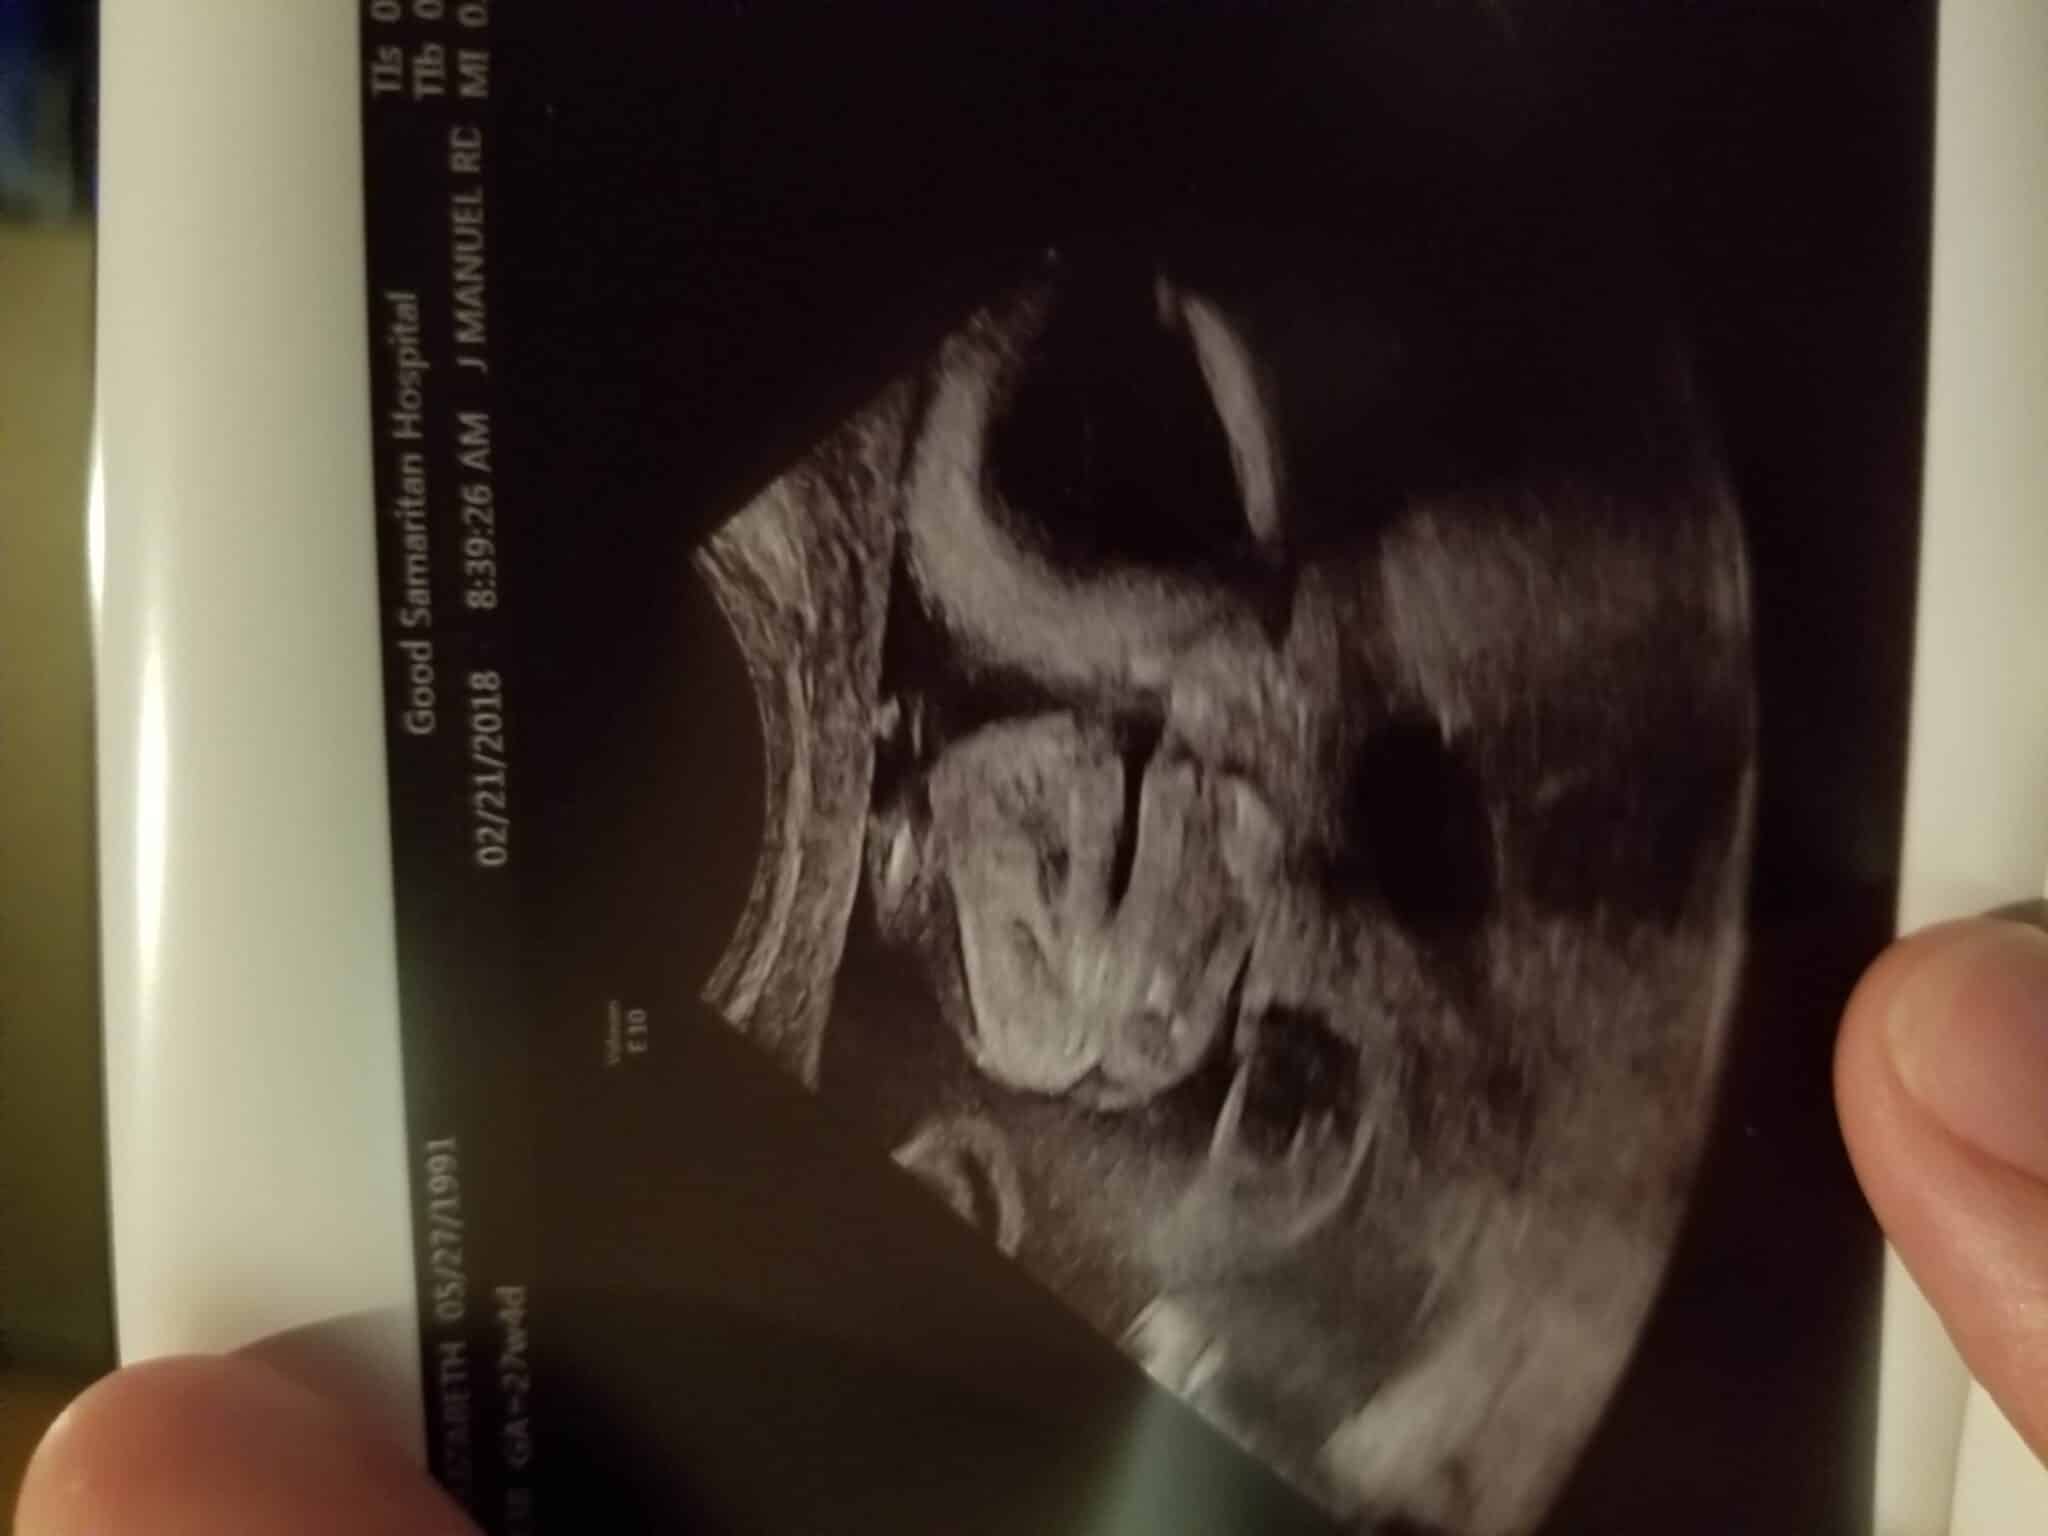

Ultrasound Photos at 27 Weeks Pregnant With Twins